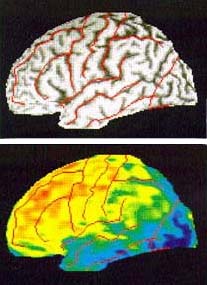

Ουάσιγκτον: Η εμφύτευση στον εγκέφαλο γενετικά τροποποιημένων κυττάρων φαίνεται να ανοίγει νέους ορίζοντες στη μάχη για την αντιμετώπιση της νόσου Αλτσχάιμερ, σύμφωνα με μελέτη που παρουσιάστηκε στο συνέδριο της Αμερικανικής Ακαδημίας Νευρολογίας.